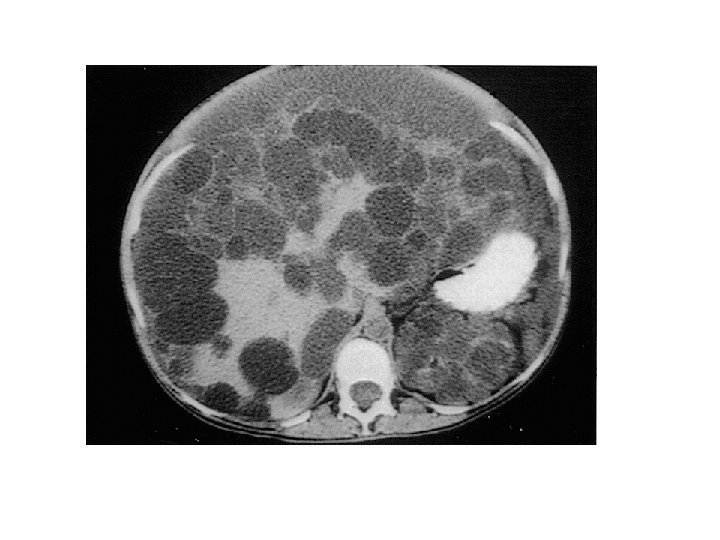

Rene policistico infantile (ARPKD: Autosomic Recessive PKD) • 1 ogni 20000 nascite • Gene anomalo: fibrocistina (PKHD 1) 6 p 21 -23 • Cisti sacciformi – 1 -2 mm x 1 -8 mm – Dotti collettori – Disgenesia biliare ARPKD in un neonato. L’ecografia ad alta risoluzione, pannello superiore, mostra dotti collettori dilatati (frecce) a disposizione radiale. La TAC contrasto (pannello inferiore) mostra un nefrogramma striato.

Cisti midollari e dotti collettori dilatati. Prominente dilatazione dei dotti midollari.